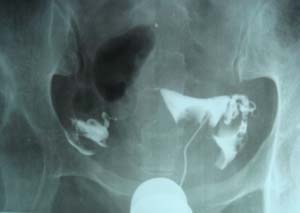

双侧输卵管是通的。

子宫输卵管造影未见明确异常。

子宫腔光整,双侧输卵管通畅,盆腔内造影剂弥散可。

各位子宫内是有个圆形充盈缺损,子宫呈倒“三角形”形态没有完全被造影剂充盈呀。子宫肌瘤。应该在拍两张斜位就好了 。

子宫体确有充盈缺损。考虑子宫肌瘤。子宫左倾

子宫输卵管造影未见明显异常,宫内充盈负影为气囊压迫所致。